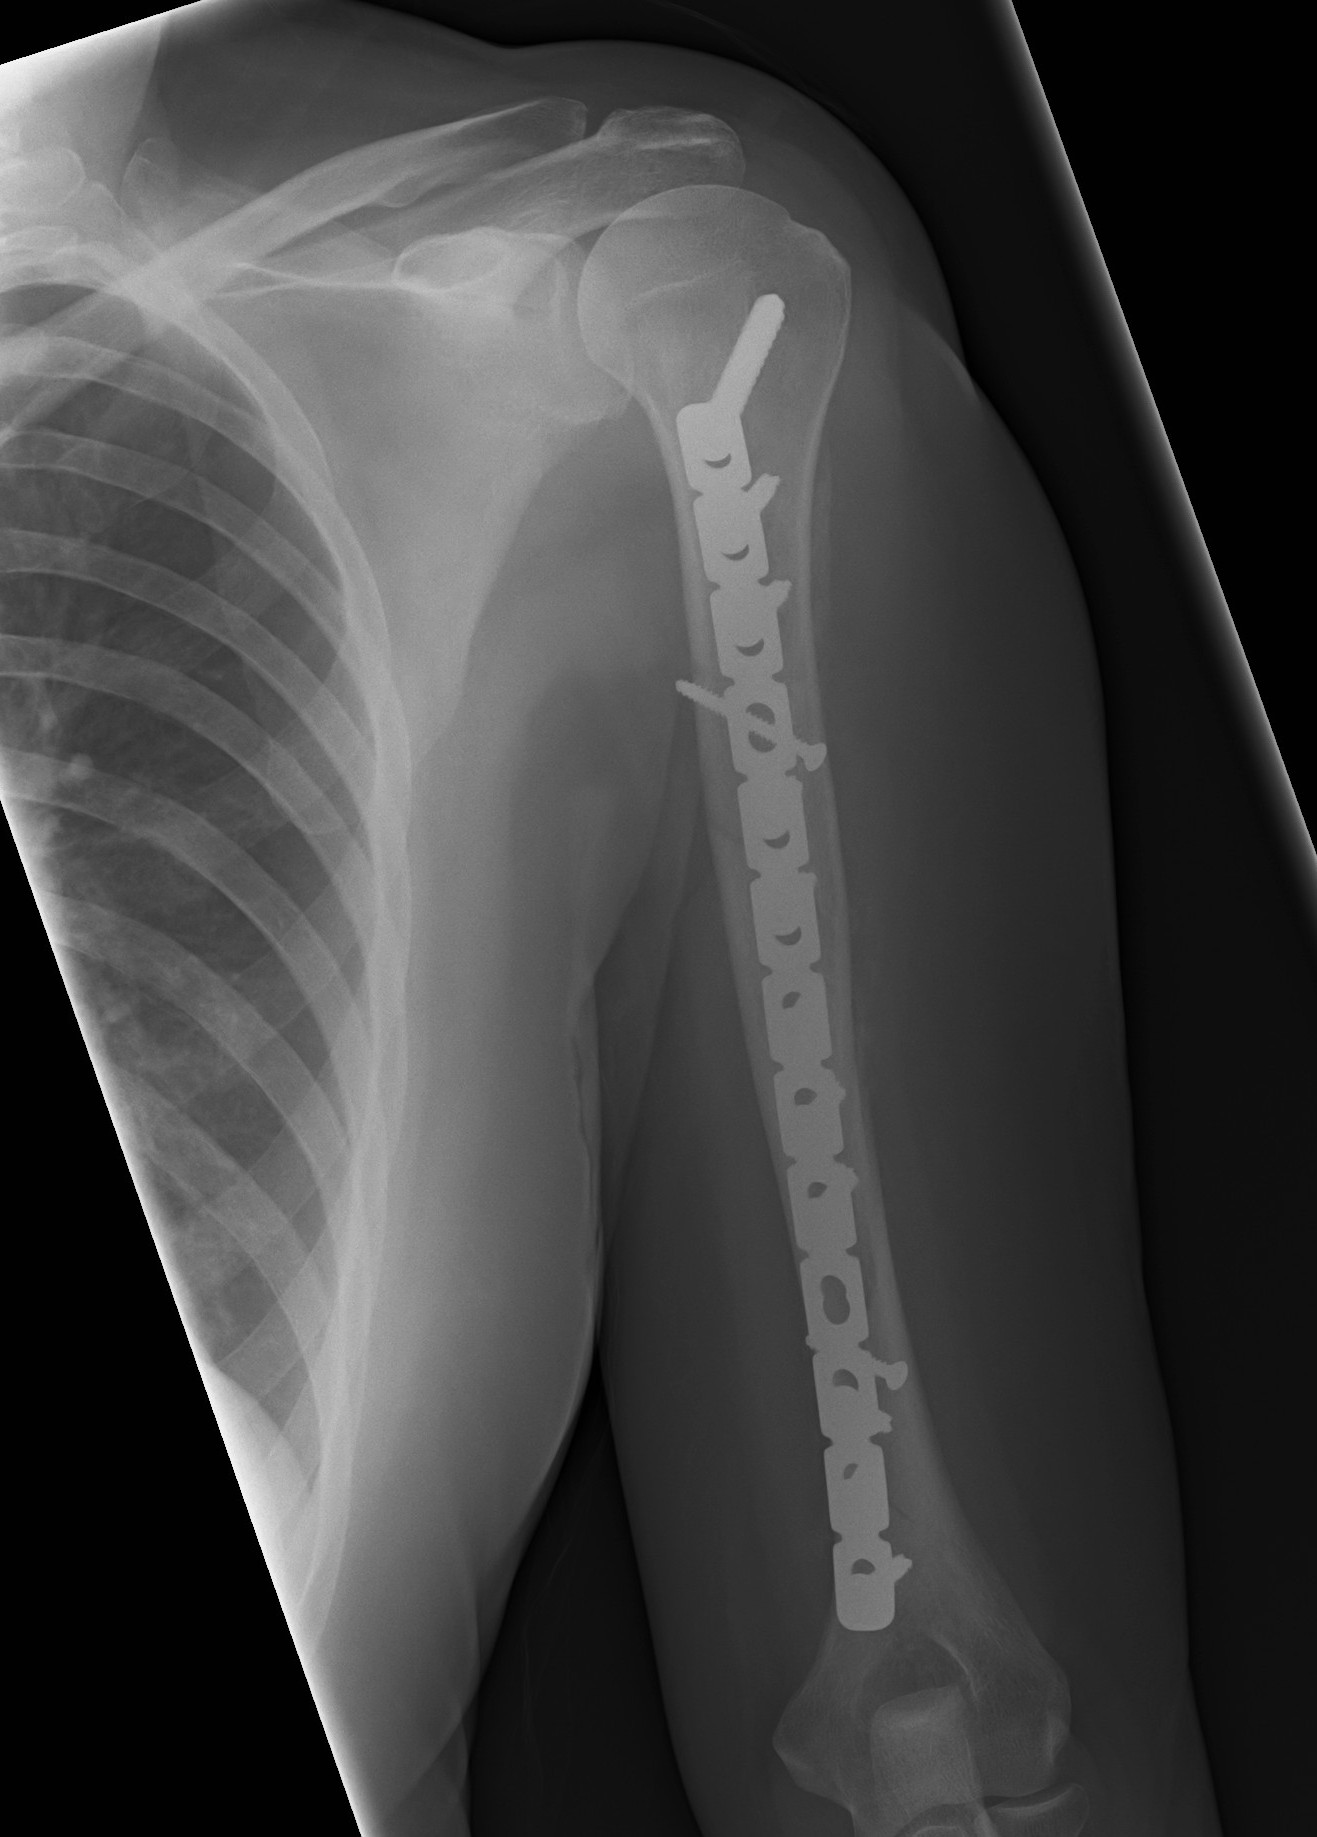

Humeral Fracture SegmentalHumeral Plate LateralHumeral Plate Long AP

Segmental fracture ORIF

Prox humerus 1Prox humerus 2Prox humerus ORIFProximal humerus ORIF

Proximal third humerus ORIF of nonunion